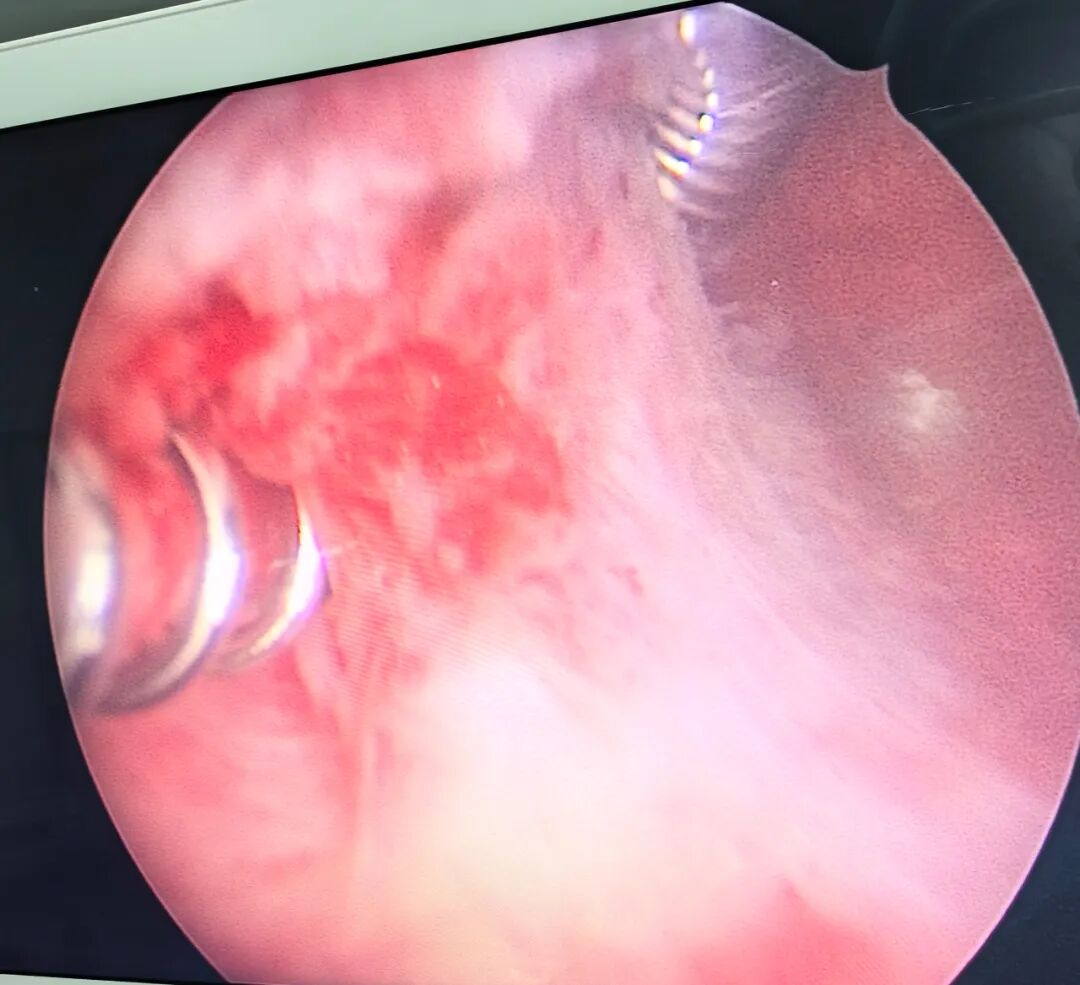

▲患者术中

术中发现患者因绝经导致生殖道萎缩,显著增加了手术难度。面对阴道狭窄、宫颈扩张困难等问题,我院省医派驻专家、妇产科副主任马啸与曾秋兰副主任医师在尝试常规取环方法未能成功之后,转而借助宫腔镜进行反复探查,发现节育环被一层黏连带紧密包裹于宫腔右侧壁。经团队讨论,决定采用宫腔镜剪刀剪开黏连带。尽管手术过程中因宫腔体积缩小、宫颈组织变硬面临诸多挑战,但凭借耐心细致的操作,最终顺利取出节育环并一并切除了内膜息肉。